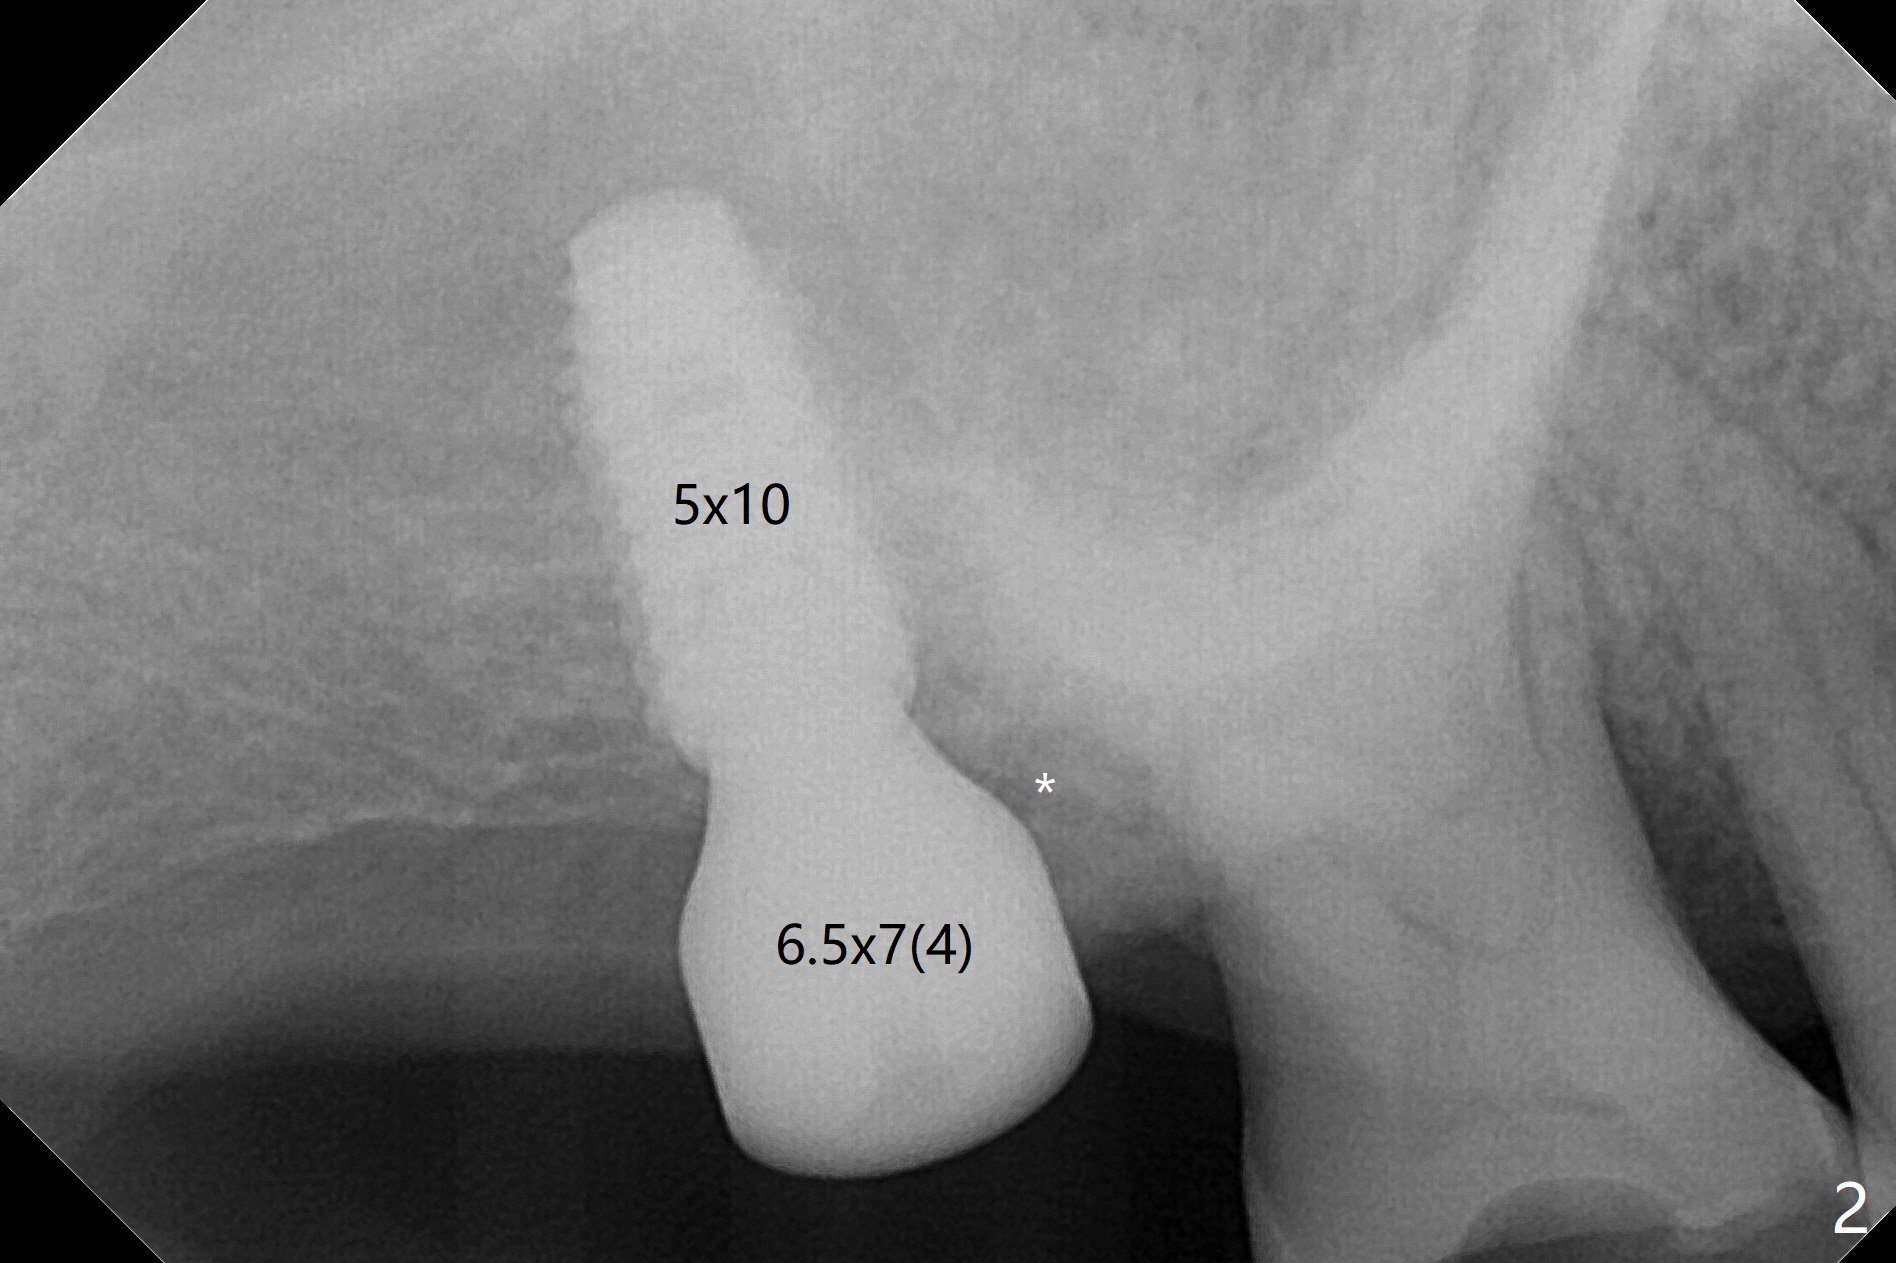

Two things happen immediately before this surgery. A SM implant is found to fail related to bruxism and poor oral hygiene, ~ 5 years in function; a UF implant will be used instead. DIO Sinus Approach Kit has not been autoclaved; therefore the free-hand one has to be used with caution. In fact the procedure goes on apparently smoothly in spite of the fact that the patient with medical knowledge is nervous about the risk of sinus lift. After 4.0x8.5 mm Neo Navi drill with 12 mm offset, the 3.6 mm sinus safety drill is used from 7 to 9 mm in length, followed by water balloon, PRF membranes (x2) and mixture of autogenous bone graft and allograft and 4.5x10 mm dummy implant (Fig.1). The definitive implant is placed with satisfactory stability (Fig.2), but a 6.5x7(4) mm healing abutment is close to the mesial crest (*). The former is reloaded following 6.0 mm Bone Profile Drill (Fig.3) and then is changed to a 6x6 mm IS one. The patient reports nasal hemorrhage immediately returning home, but there is no similar episode a few hours later. Re-analysis of preop (Fig.4) and immediate postop (Fig.5) CT shows that water balloon technique in fact swells the sinus membrane (M) instead elevating it. It is safe to place more bone graft (Fig.5 *). There is pain when the 6x6 mm healing abutment is being removed nearly 5 months postop (Fig.6.7). The patient complains of mild sinus discomfort, although panoramic X-ray does not show abnormality (Fig.8). He will return for recheck for implant stability (low bone density) before impression 2-4 months later.